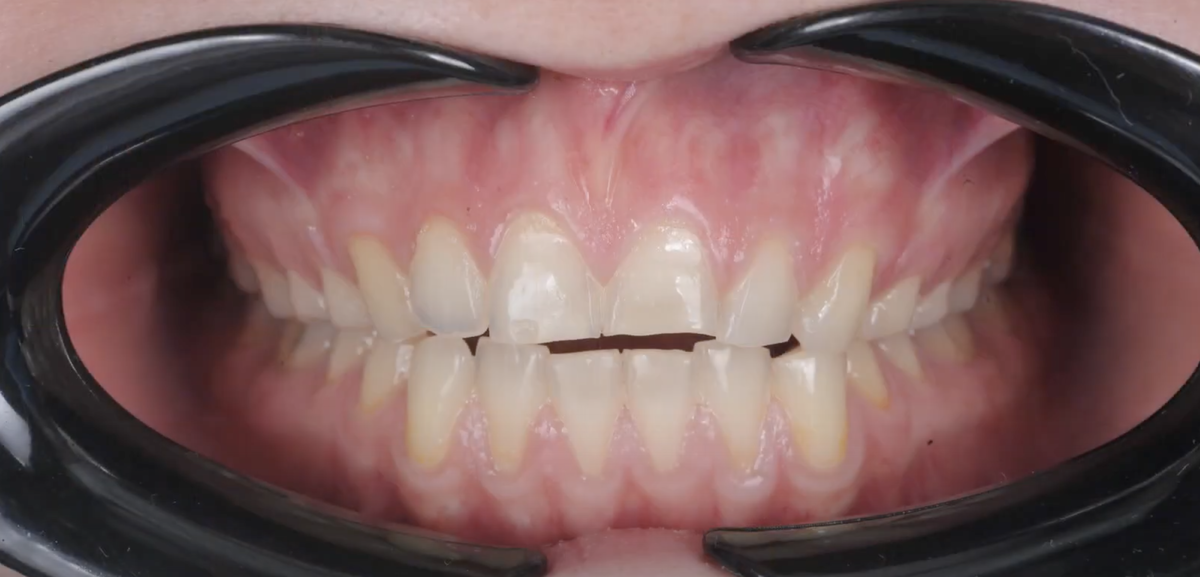

Как брекеты помогают при десневой улыбке? Нагляднее всего это покажет следующий кейс. Безусловно, здесь можно было бы прибегнуть к челюстно-лицевой хирургии, но пациентка этого не хотела. Поэтому лечение заключалось в ношении брекетов и установке специальных мини-винтов.

Основная задача в данном кейсе изначально состояла не в коррекции десневой улыбки, а в подготовке пациентки к тотальной ортопедической реставрации – установке коронок и виниров. Однако в ходе ортодонтического лечения, по мере нормализации положения зубов, стал проявляться десневой прикус.

-2

Первым этапом его коррекции стали уколы ботокса, однако результат оказался недостаточным. Пациентке хотелось полностью убрать десневую улыбку, поэтому вторым этапом стала установка четырех мини-винтов. В первые несколько дней эти винты, конечно, доставляли дискомфорт, но потом пациентка к ним привыкла, и все, что ей нужно было делать, это раз в три недели появляться в клинике для коррекции этих винтов.

-3

В итоге был получен отличный результат – пациентка после снятия брекетов полностью была готова к дальнейшей работе с ортопедом, а десневая улыбка практически ушла. Вся работа заняла около четырех месяцев.